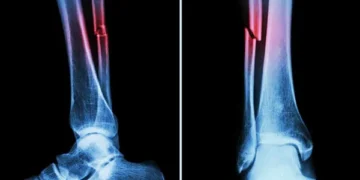

NEW DELHI: Australian and Canadian researchers have developed a cutting-edge machine learning algorithm capable of rapidly identifying heart disease and fracture risks using routine bone density scans. The innovation, developed by researchers from Australia’s Edith Cowan University (ECU) in conjunction with Canada’s University of Manitoba, could pave the way for more comprehensive and earlier diagnoses during routine osteoporosis screenings, improving outcomes for millions of older adults, Xinhua news agency reported.

The automated system analyses vertebral fracture assessment (VFA) images to detect abdominal aortic calcification (AAC) — a key marker linked to heart attacks, strokes, and falls.

Traditionally, assessing AAC requires around five to six minutes per image by a trained expert. The new algorithm slashes that time to under a minute for thousands of images, making large-scale screening far more efficient, it said.

Further research by ECU’s Marc Sim revealed that AAC is not only a cardiovascular risk indicator but also a strong predictor of falls and fractures. In fact, AAC outperformed traditional fall risk factors like bone mineral density and past fall history.

“The higher the calcification in your arteries, the higher the risk of falls and fractures,” Sim said, adding clinicians typically overlook vascular health in fall assessments, and this algorithm changes that.

“Our analysis uncovered that AAC was a very strong contributor to fall risks and was actually more significant than other factors that are clinically identified as fall risk factors.”